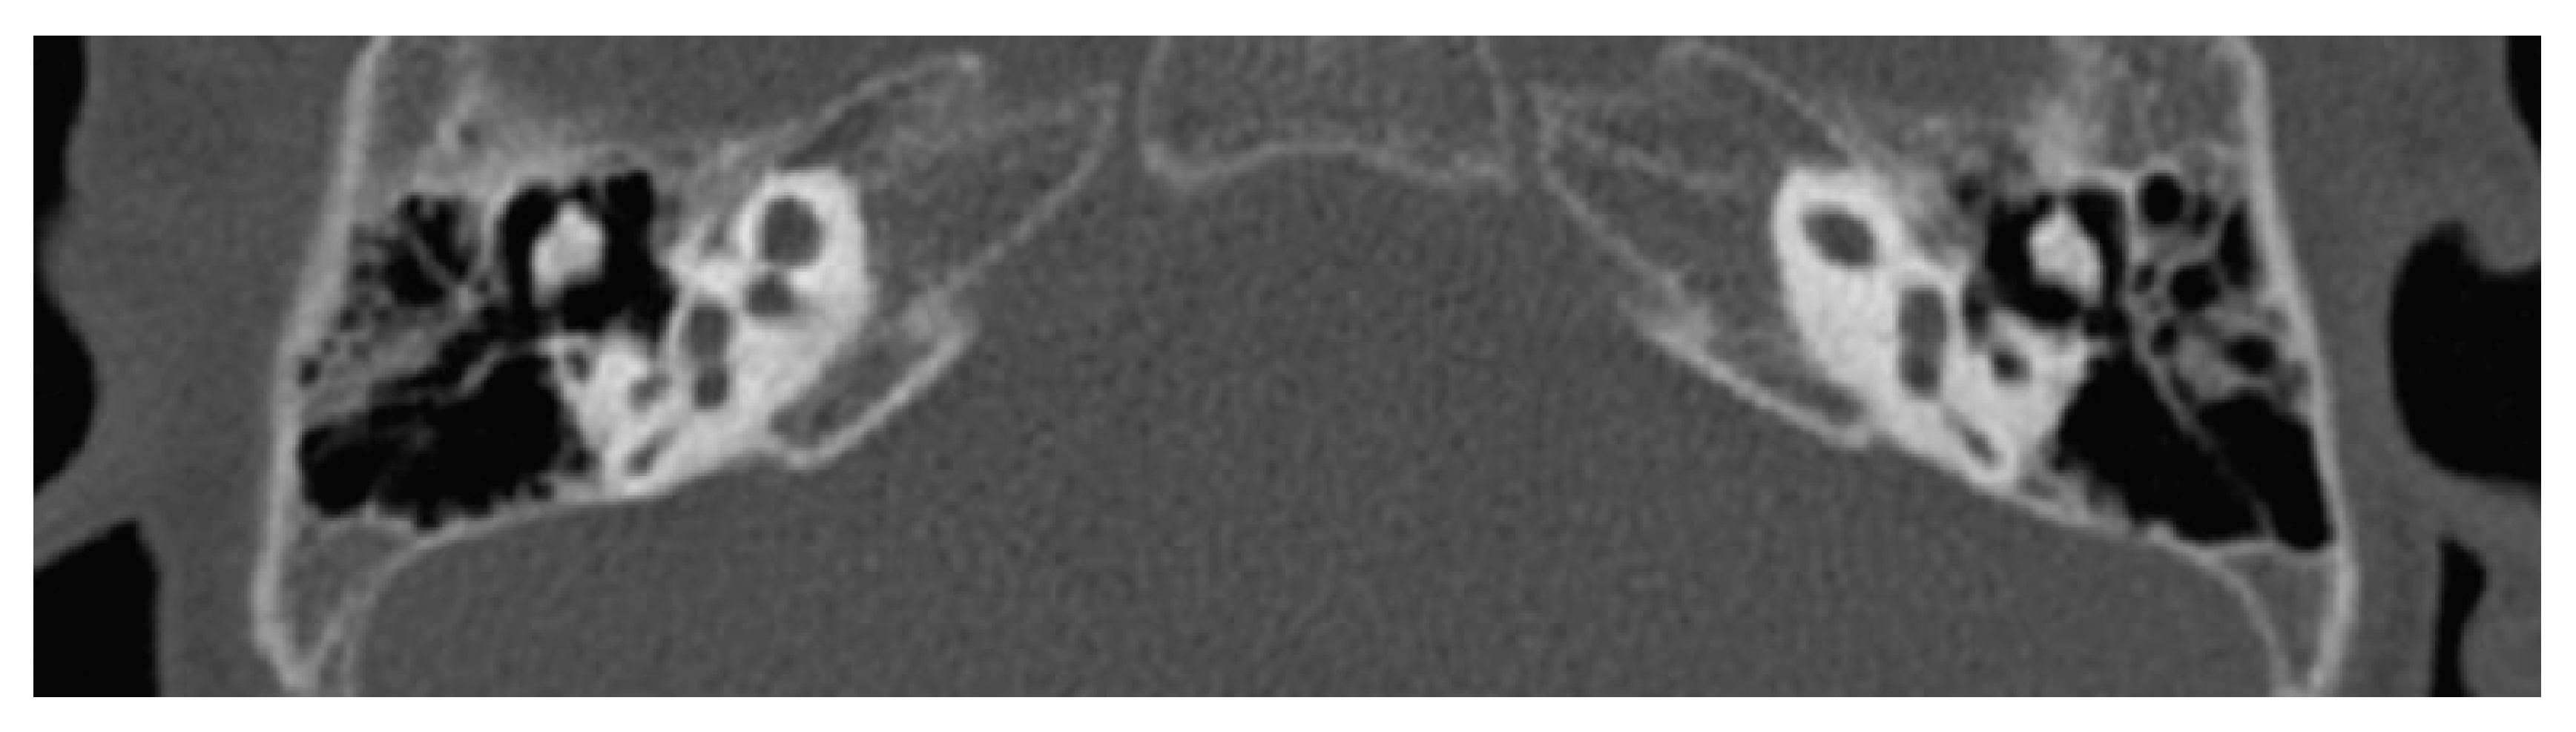

6.1. Incomplete Partition Type 1